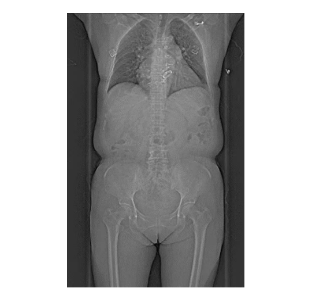

支持“無禁忌”全身檢查,尤其適合急癥患者(如急性胸痛、胸痛三聯(lián)征)的“一站式”快速檢查,為搶救贏得黃金時(shí)間。

檢查無需藥物控制心率或長時(shí)間準(zhǔn)備,減少等待焦慮。80cm超大掃描范圍,肥胖或特殊體位患者亦可輕松完成檢查。